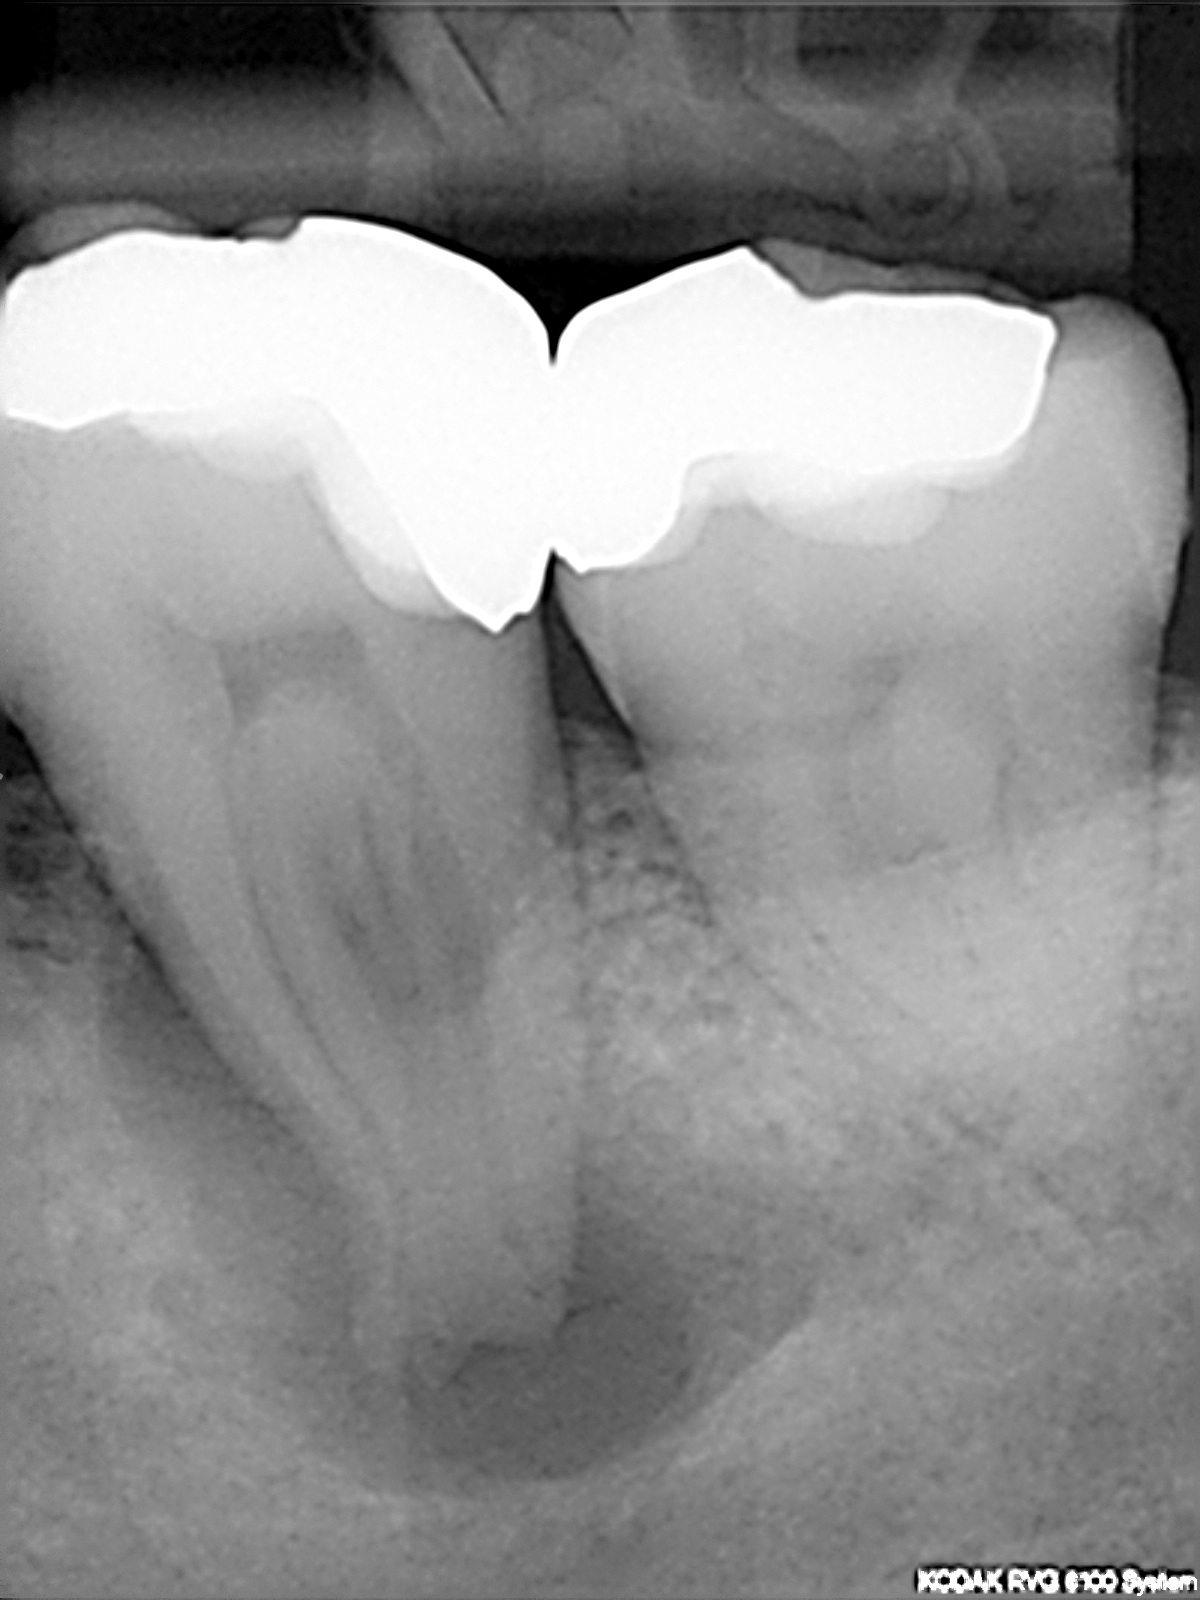

Ausgangsbild

Interessante Kanalanatomie (2)